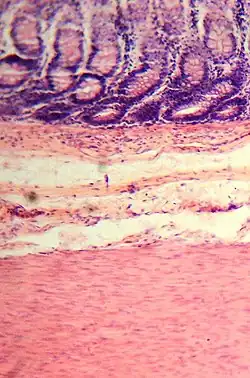

Histología del intestino grueso

Presenta criptas de Lieberkühn, no tiene vellosidades ni pliegues circulares.[44]

En el intestino grueso hay una gran cantidad de exocrinocitos caliciformes. Las poblaciones celulares epiteliales son las mismas del intestino delgado.[45][46]

Neuronas estrelladas eferentes multipolares heterópodas forman parte de los ganglios intraparietales parasimpáticos.[47][48][49]

Presenta, en la superficie exterior (túnica serosa), evaginaciones. Una evaginación llena de tejido adiposo constituye un apéndice omental.